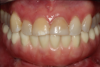

Figure 3 shows a ti-base connection, narrow emergence profile of the zirconia abutment (pink characterization), and final abutment with margins that were computer-generated and computer-manufactured to reflect the appropriate soft-tissue architecture for the patient. As shown in Figure 4, the abutment was seated and torqued to 25 Nm, allowed to rest for 10 minutes, and torqued once again to 25 Nm. The crown was tried in, fit was verified, and occlusion was established. This particular patient was concerned that the implant crown and implant would not look natural. Before beginning the single-tooth replacement with implant dentistry, a diagnostic wax-up and photographic imaging were employed to help develop a natural-looking provisional during the osseointegration phase. A treatment plan was developed and presented to the patient for considering cosmetic dentistry for tooth Nos. 6 through 11. The patient was still apprehensive and chose to begin therapy for only tooth No. 8. Since the final seat date, the patient has been very satisfied with the results of the single-tooth therapy and has committed to completing the cosmetic dentistry services for tooth Nos. 6 through 11.

Fig 4. Seated abutment (left) and crown try-in (right).

Figure 4